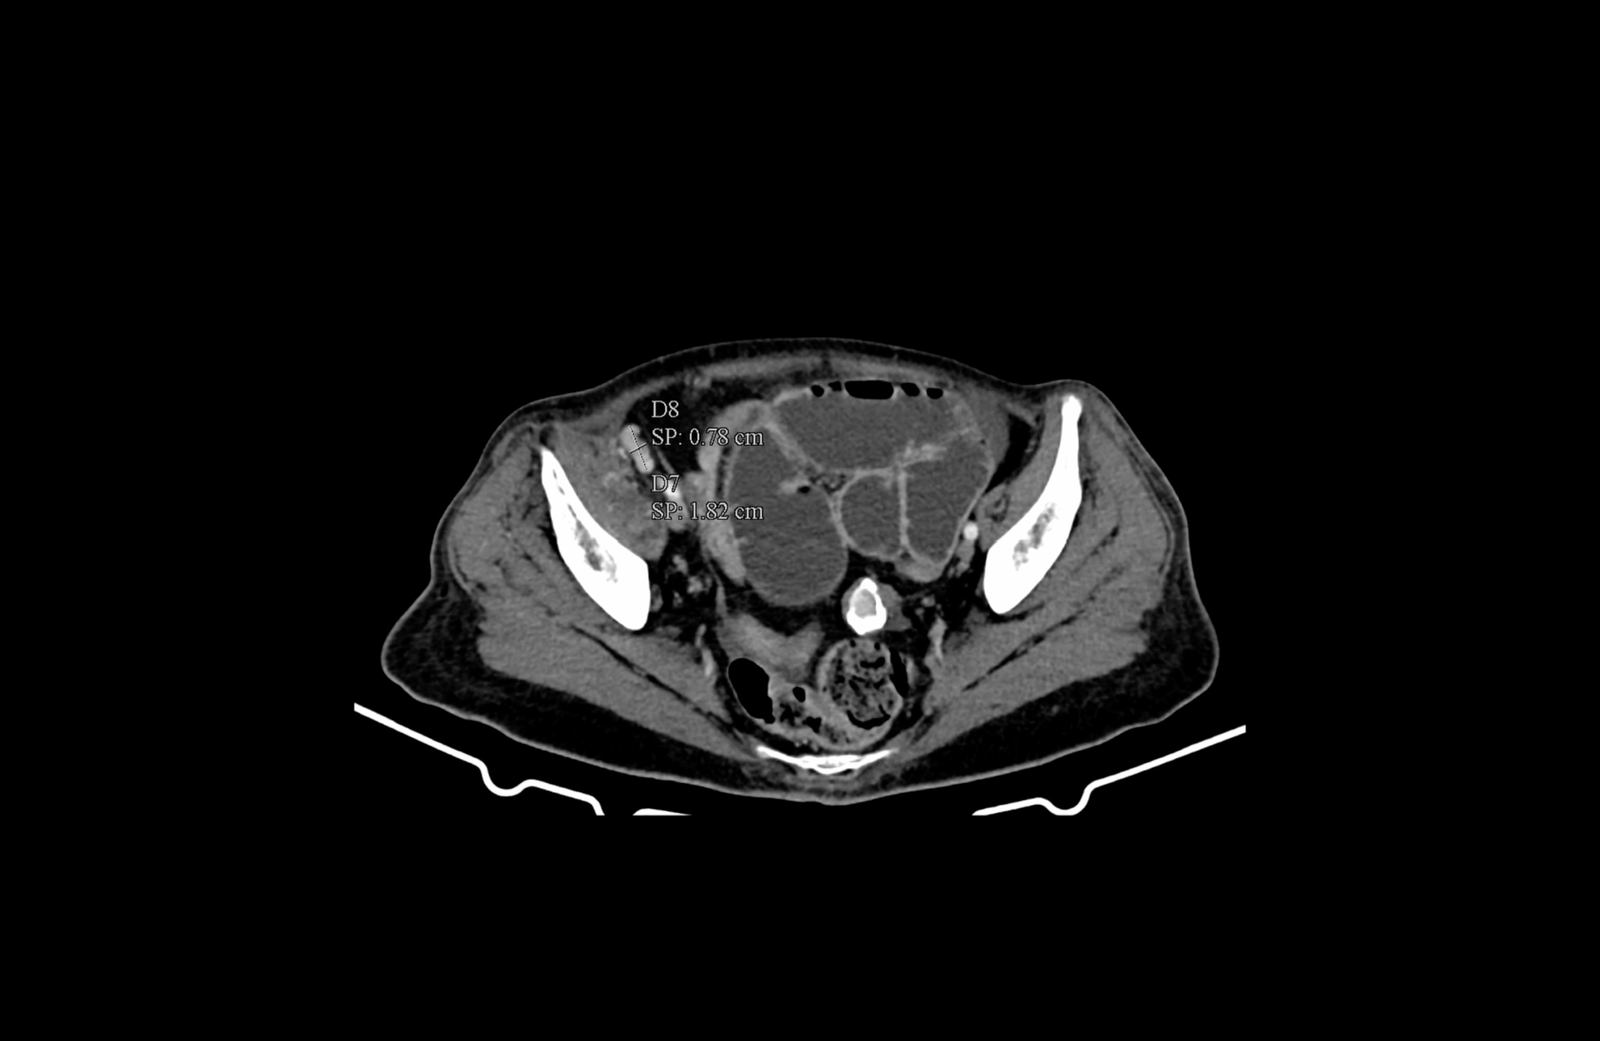

Извърши се компютърна томография на корем и малък таз, която установи:

- локално авансирала туморна формация на десния колон с огромни размери

- механичен илеус с пълен стоп в дисталния отдел на тънките черва с прераздути и оточни тънкочревни бримки, по цялата им дължина

- локорегионална метастатична лимфаденомегалия обтураторно, параилиачно, ретроперитонеално до нивото на бъбречните съдове

- инфилтрация на мастната бъбречна капсула в дясно

- инфилтрация на предната коремна стена

- инфилтрация на m. psoas major и n. femoralis

- инфилтрация на m. iliacus, граничеща с илиачната кост

- ангажиране на вътрешната илиачна съдова дъга

- инфилтрация на тънкочревни бримки от дисталния илеум по съседство

- не се откриха паренхимни метастази

Авансирала туморна формация на десния колон, на фона на силно раздути тънкочревни бримки, в условията на механичен илеус

Медиална компресия и деформиране на лумените на десните общи и външни илиачни съдове. Прорастване на тумора през цялата дебелина на m. iliacus

Инфилтрация на меките тъкани на предната коремна стена

Инфилтрация на меките тъкани на предната коремна стена и m. iliopsoas, както и прилежащия към него n. femoralis

Параилиачна лимфаденомегалия с размер на възлите до 2см.

Ретроперитонеална лимфаденомегалия, суспектна за малигнена.